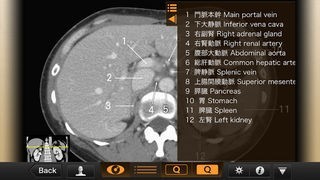

• 矢印が引かれているから場所がわかりやすい

CT・MRI解体新書のスクリーンショット

App Storeより引用